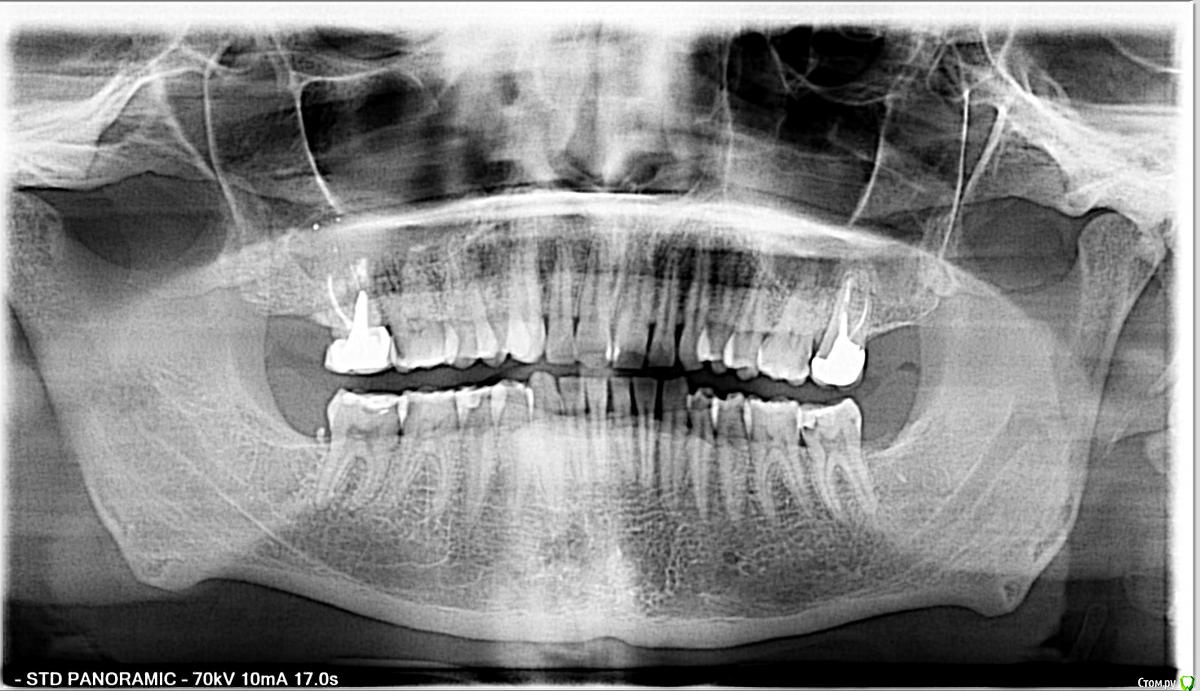

pogoreliy Опубликовано 5 июля, 2017 Автор Поделиться Опубликовано 5 июля, 2017 (изменено) Доброго всем утра. Занимаюсь на данный момент зубом, в рамках чего была сделана КТ. Хотелось бы узнать мнение сообщества о ней. Изменено 5 июля, 2017 пользователем pogoreliy Ссылка на комментарий

Bier Опубликовано 5 июля, 2017 Поделиться Опубликовано 5 июля, 2017 05.07.2016 была сделана та самая панорама, через несколько недель после которой зуб раскрошился. 26.08 мне уже поставили пломбу. Если верить моей, васяпупкинской интерпретации снимков, то кариес до пульпы так и не добрался, чего нельзя сказать о бормашине врача. Разве что микробы совершили трудовой подвиг за эти полтора месяца.на этом панорамном снимке уже есть здоровый кариес. И хр. пульпит. Ссылка на комментарий

Bier Опубликовано 5 июля, 2017 Поделиться Опубликовано 5 июля, 2017 Доброго всем утра. Занимаюсь на данный момент зубом, в рамках чего была сделана КТ. Хотелось бы узнать мнение сообщества о ней.на зубе 3.7 уже периодонтит, т.е. нерв в зубе уже умересть еще проблема на 1.7 - там здоровенная киста. Ссылка на комментарий

pogoreliy Опубликовано 5 июля, 2017 Автор Поделиться Опубликовано 5 июля, 2017 (изменено) Спасибо за внимание! на зубе 3.7 уже периодонтит, т.е. нерв в зубе уже умерА чего у него там, паразита, в таком случае болеть изволит? есть еще проблема на 1.7 - там здоровенная киста.Ну зашибись Это шарик такой грибообразный? Изменено 5 июля, 2017 пользователем pogoreliy Ссылка на комментарий